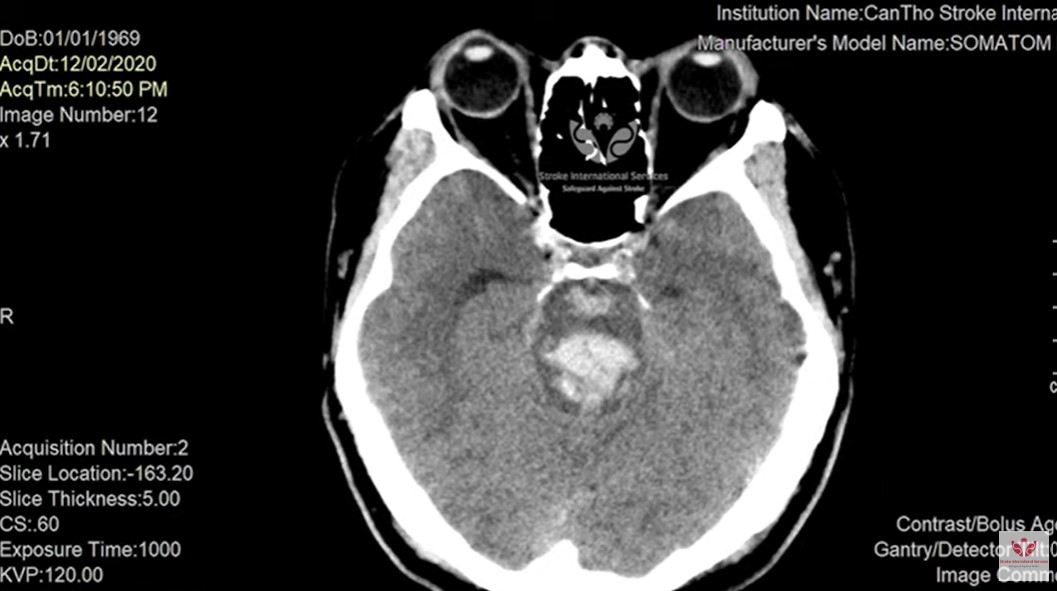

TS.BS Trần Chí Cường trả lời: Chúng ta cần theo dõi bệnh nhân, nếu đang điều trị bệnh lý nền như tim mạch, huyết áp, tiểu đường thì phải kiểm soát các chỉ số và điều trị tích cực hơn. Một trong những yếu tố khiến đường huyết, huyết áp tăng cao và khó kiểm soát hơn trong thời tiết lạnh là do người bệnh ngủ nhiều, lười vận động. Đây là yếu tố nguy cơ dẫn đến hiệu quả xấu như đột quỵ. Do đó cần phải thay đổi lại lối sống, sinh hoạt khoa học hơn. Tại bệnh viện S.I.S Cần Thơ cũng từng ghi nhận nhiều bệnh nhân hôn mê vì bị tăng đường huyết trong mùa lạnh. Một số trường hợp đường huyết lên tới 700mg/dL hoặc 300mg/dL khiến bệnh nhân hôn mê. Nếu không cấp cứu kịp thời, việc hôn mê do tăng đường huyết sẽ diễn tiến nặng và tử vong. Ví dụ một bệnh nhân nam, 51 tuổi nhập viện do đau đầu, sau đó lơ mơ và hôn mê. Hình ảnh cho thấy bệnh nhân bị xuất huyết não nặng nề. Vị trí xuất huyết não xảy ra ở vùng cầu não, sau đó bệnh nhân tử vong trong 24 giờ sau khi nhập viện.bệnh nhân đột quỵTrường hợp đáng tiếc thứ 2 là bệnh nhân nam 29 tuổi, nhập viện trong tình trạng hôn mê sâu. Trên hình ảnh chụp CT phát hiện phình mạch máu não khổng lồ 5cm và túi phình đã bị xuất huyết, lượng máu phun ra ngoài. Đây là trường hợp khiến chúng ta bị động. Mặc dù chúng tôi cố điều trị hết sức nhưng vài ngày sau, bệnh nhân đã tử vong. Đây là trường hợp đáng tiếc. Những ai có túi phình não trong mùa lạnh sẽ có nguy cơ bị xuất huyết não. Vì vậy cần tầm soát tốt khi bệnh nhân có triệu chứng về đau đầu.